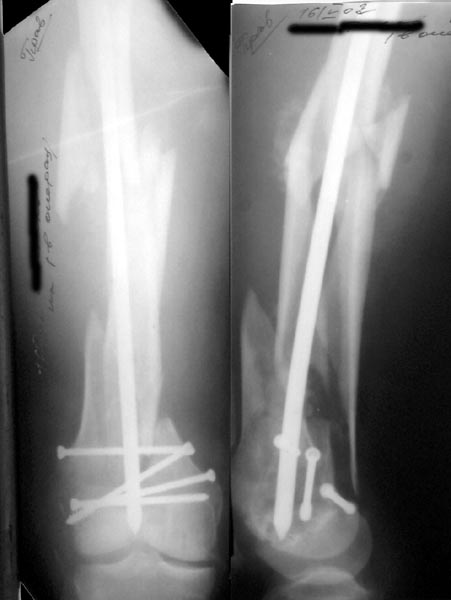

Re: Многооскольчатое бедро

А> Попробуй ретроградно интрамедуллярный гвоздь с блокированием

Нету у нас (пока?) гвоздей для ретроградного введения. Доводилось слышать, что можно любые гвозди вводить ретроградно, но как-то не

получается пока преодолеть психологический барьер. В основном потому, что не могу для себя уяснить преимущества введения через колено

обычного UFN. Или, как коллеги из Индии рассказывали, кое-кто вводит UTN в бедро ретроградно.

ЛА> и увеличенным количеством винтов дистально или как ты любишь miss

ЛА> a nail.

Да, примерно так и сделали. Надо было, пожалуй, кончик гвоздя еще спилить, чтобы отверстие было еще дистальнее. Англоязычные коллеги еще

советовали винты в передне-заднем направлении вводить, но что-то не увидел, где там подходящее место.